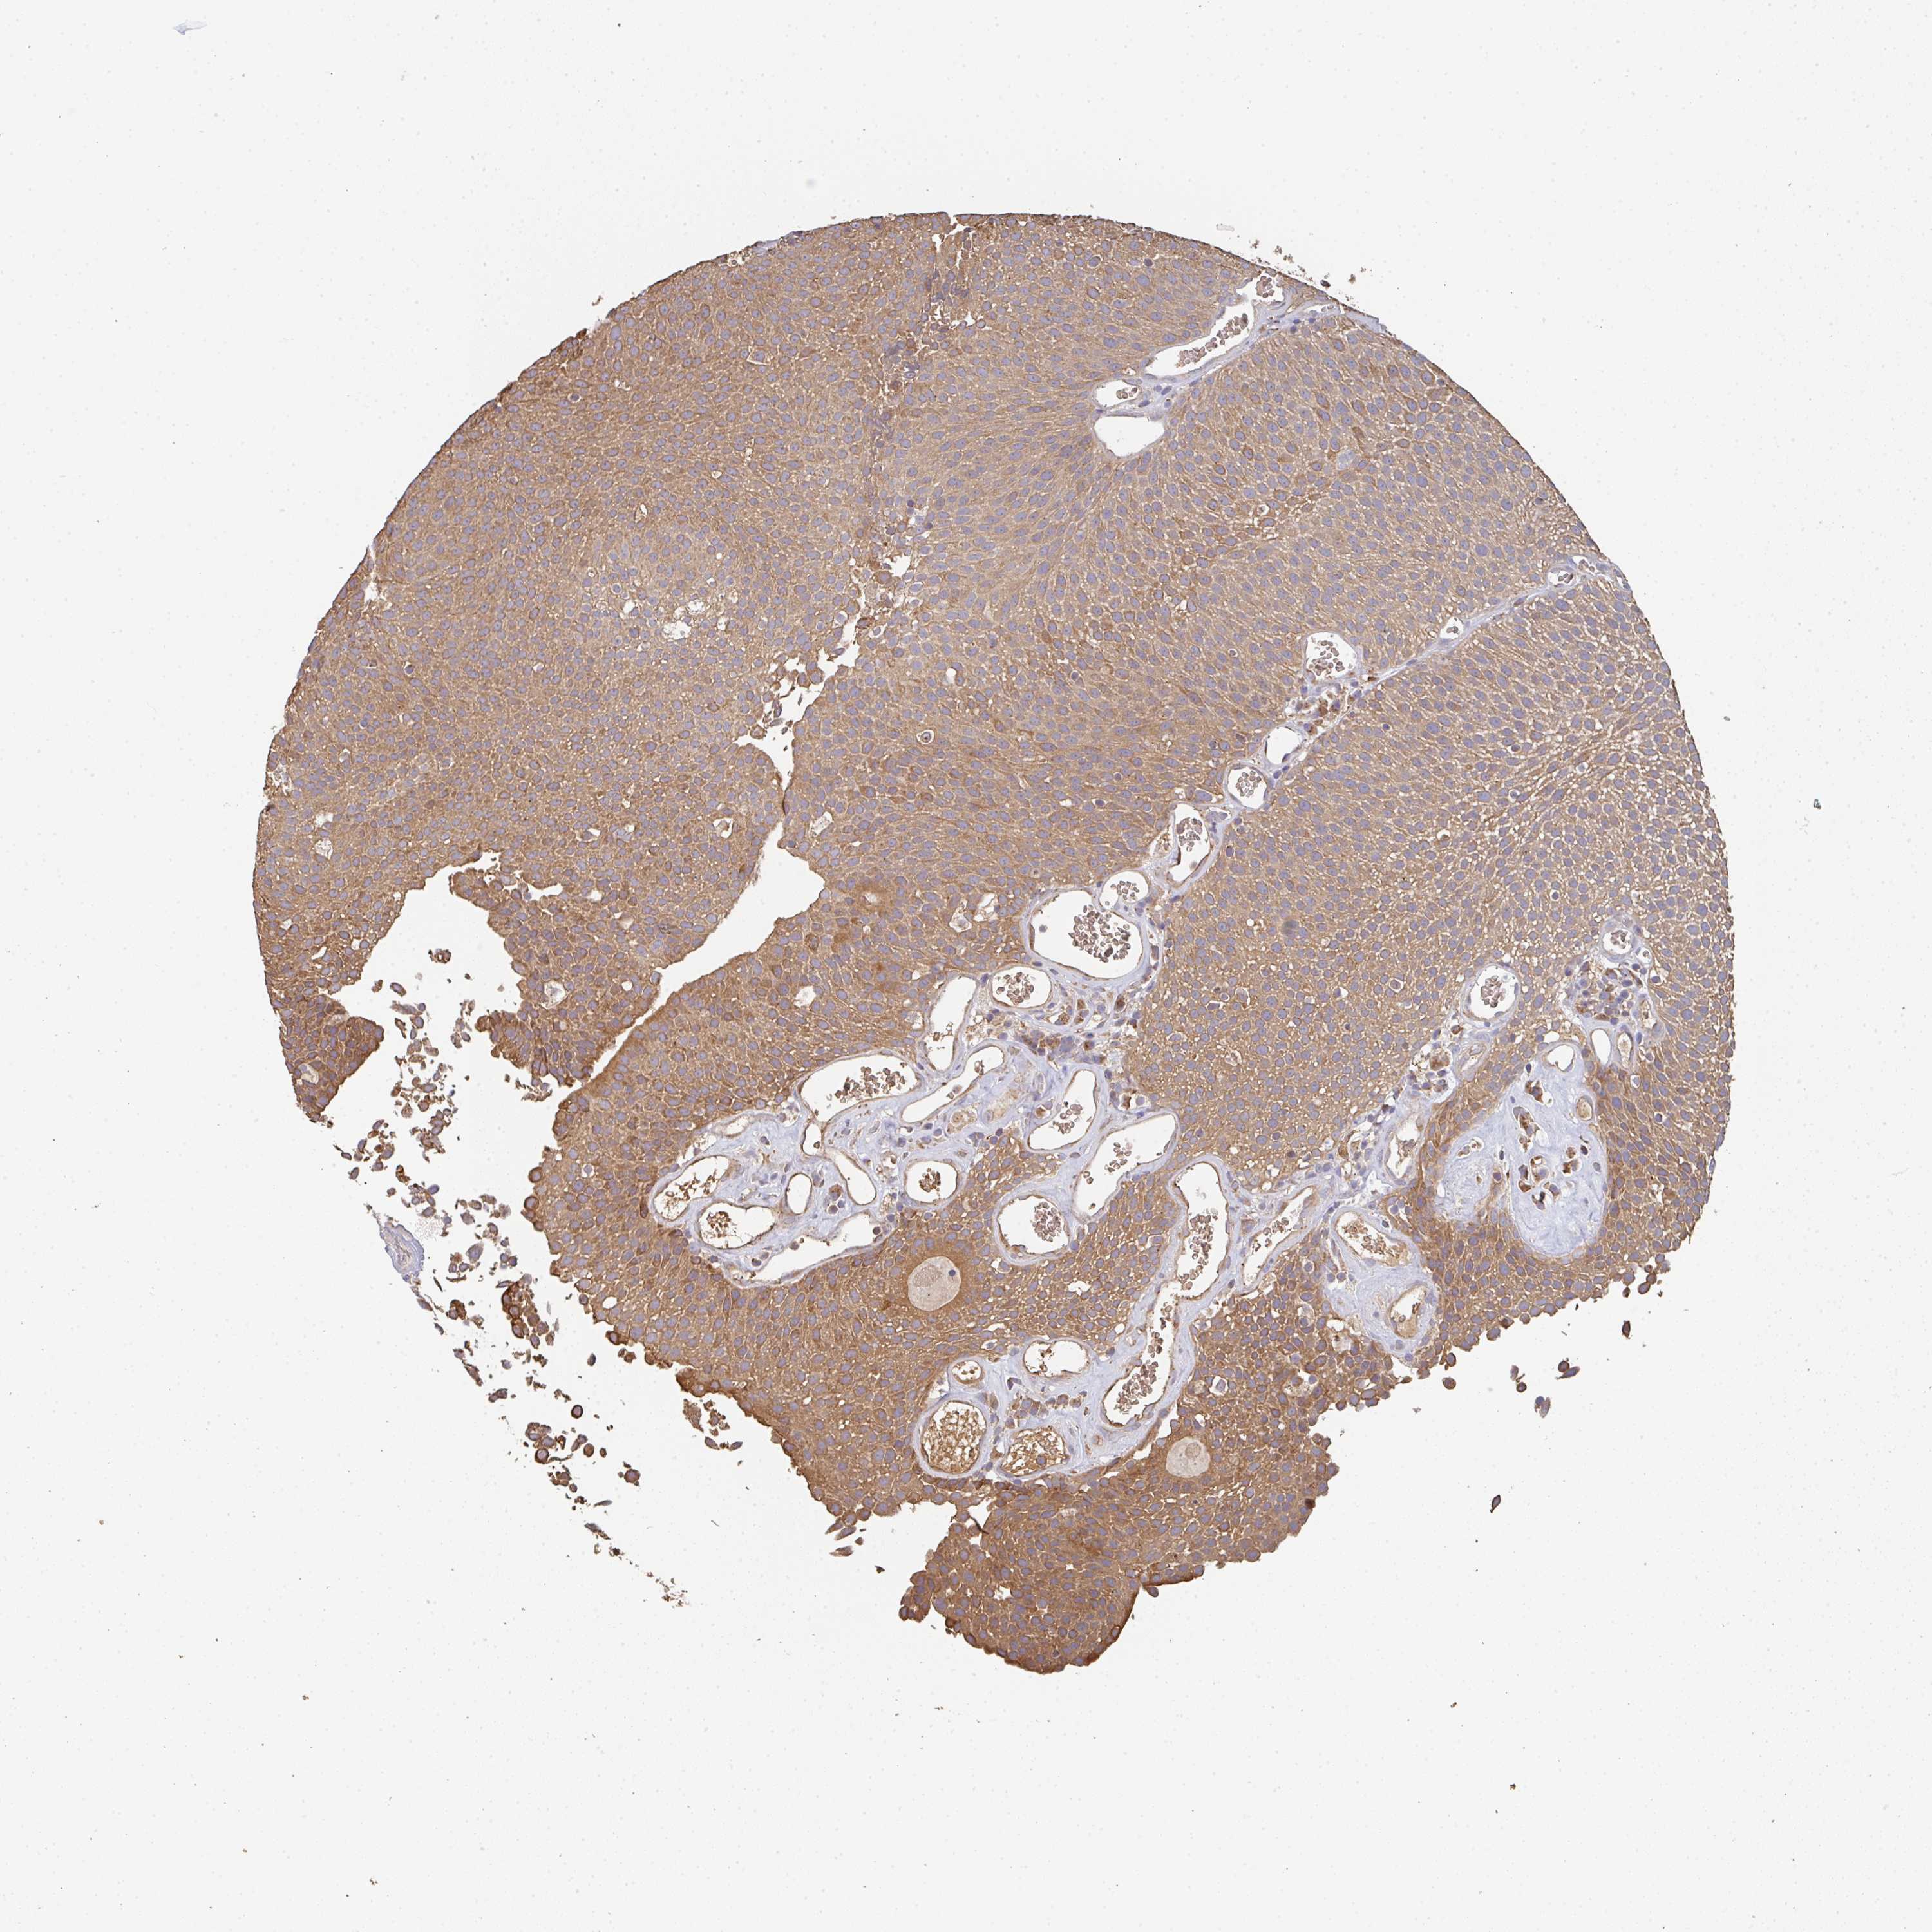

UROTHELIAL CANCER - Protein expressioni

A mouse-over function shows sample information and annotation data. Click on an image to view it in a full screen mode. Samples can be filtered based on level of antibody staining by selecting one or several of the following categories: high, medium, low and not detected. The assay and annotation is described here.

Antibody stainingi

Antibody staining in the annotated cell types in the current human tissue is reported as not detected, low, medium, or high, based on conventional immunohistochemistry profiling in selected tissues. This score is based on the combination of the staining intensity and fraction of stained cells.

Each image is clickable and will lead to virtual microscopy that enables deeper exploration of all samples and also displays staining intensity scores, fraction scores and subcellular localization as well as patient and tissue information for each sample.

Antibody HPA056821

Staining

High

Medium

Low

Not detected

Intensity

Strong

Moderate

Weak

Negative

Quantity

>75%

75%-25%

<25%

None

Location

Nuclear

Cytoplasmic/membranous

Cytoplasmic/membranous,nuclear

Urothelial carcinoma, High grade

Urothelial carcinoma, Low grade